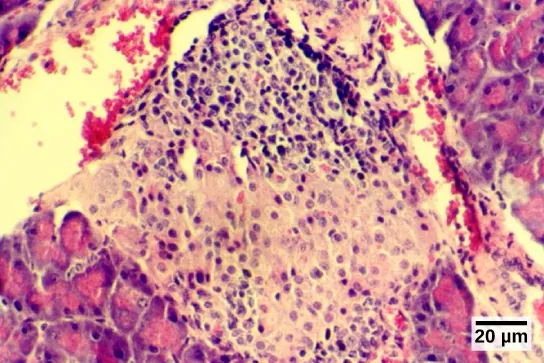

The endocrine cells of the pancreas form clusters called pancreatic islets or the islets of Langerhans, as visible in the micrograph shown in Figure 28.20. The pancreatic islets contain two primary cell types: alpha cells, which produce the hormone glucagon, and beta cells, which produce the hormone insulin. These hormones regulate blood glucose levels. As blood glucose levels decline, alpha cells release glucagon to raise the blood glucose levels by increasing rates of glycogen breakdown and glucose release by the liver. When blood glucose levels rise, such as after a meal, beta cells release insulin to lower blood glucose levels by increasing the rate of glucose uptake in most body cells, and by increasing glycogen synthesis in skeletal muscles and the liver. Together, glucagon and insulin regulate blood glucose levels.

Micrograph shows purple-stained cells in a white tissue. The white tissue is surrounded by tissue that stains pink.

Figure 28.20 The islets of Langerhans are clusters of endocrine cells found in the pancreas; they stain lighter than surrounding cells. (credit: modification of work by Muhammad T. Tabiin, Christopher P. White, Grant Morahan, and Bernard E. Tuch; scale-bar data from Matt Russell)